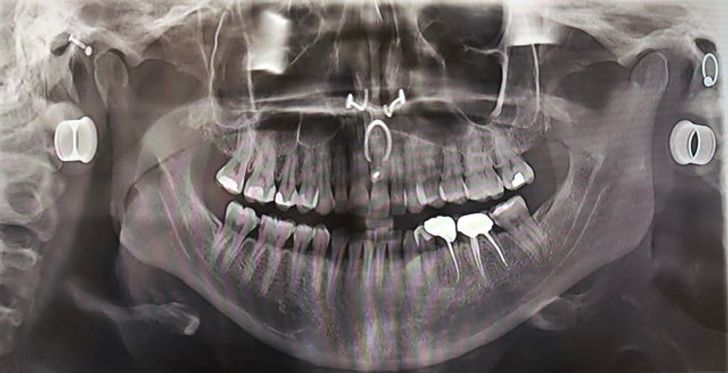

«Мій рентгенівський знімок зубів, зроблений приблизно 2 місяці тому. Дантист отримав від цього справжнє задоволення»

“Моя улюблена знахідка – пірсинг”